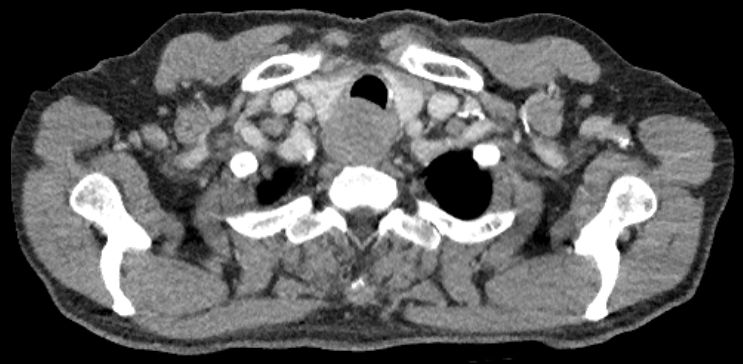

| Ösophagus | 68-jähriger Mann mit einem okkludierenden Tumor des oberen Ösophagus mit Infiltration der Trachea.![]() | |||||||||||||||||||